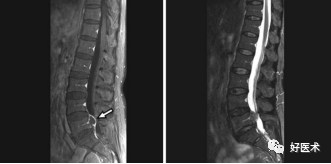

我们先来看一个病例:

诊断